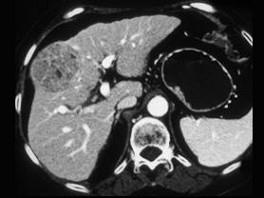

女,55岁,右上腹痛,消瘦乏力3个月,请结合图像诊断为 ( )A、肝脓肿B、肝转移癌C、肝腺瘤D、肝癌E、肝血管瘤单选题

问题 女,55岁,右上腹痛,消瘦乏力3个月,请结合图像诊断为 ( )

选项 A、肝脓肿 B、肝转移癌 C、肝腺瘤 D、肝癌 E、肝血管瘤 单选题

答案 D